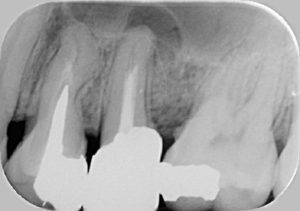

※根の治療は、根の先まで白いクスリが入っていないと感染しやすくなり、膿の袋(黒い影)が出来てしまうことが非常に多いです!

↓↓↓